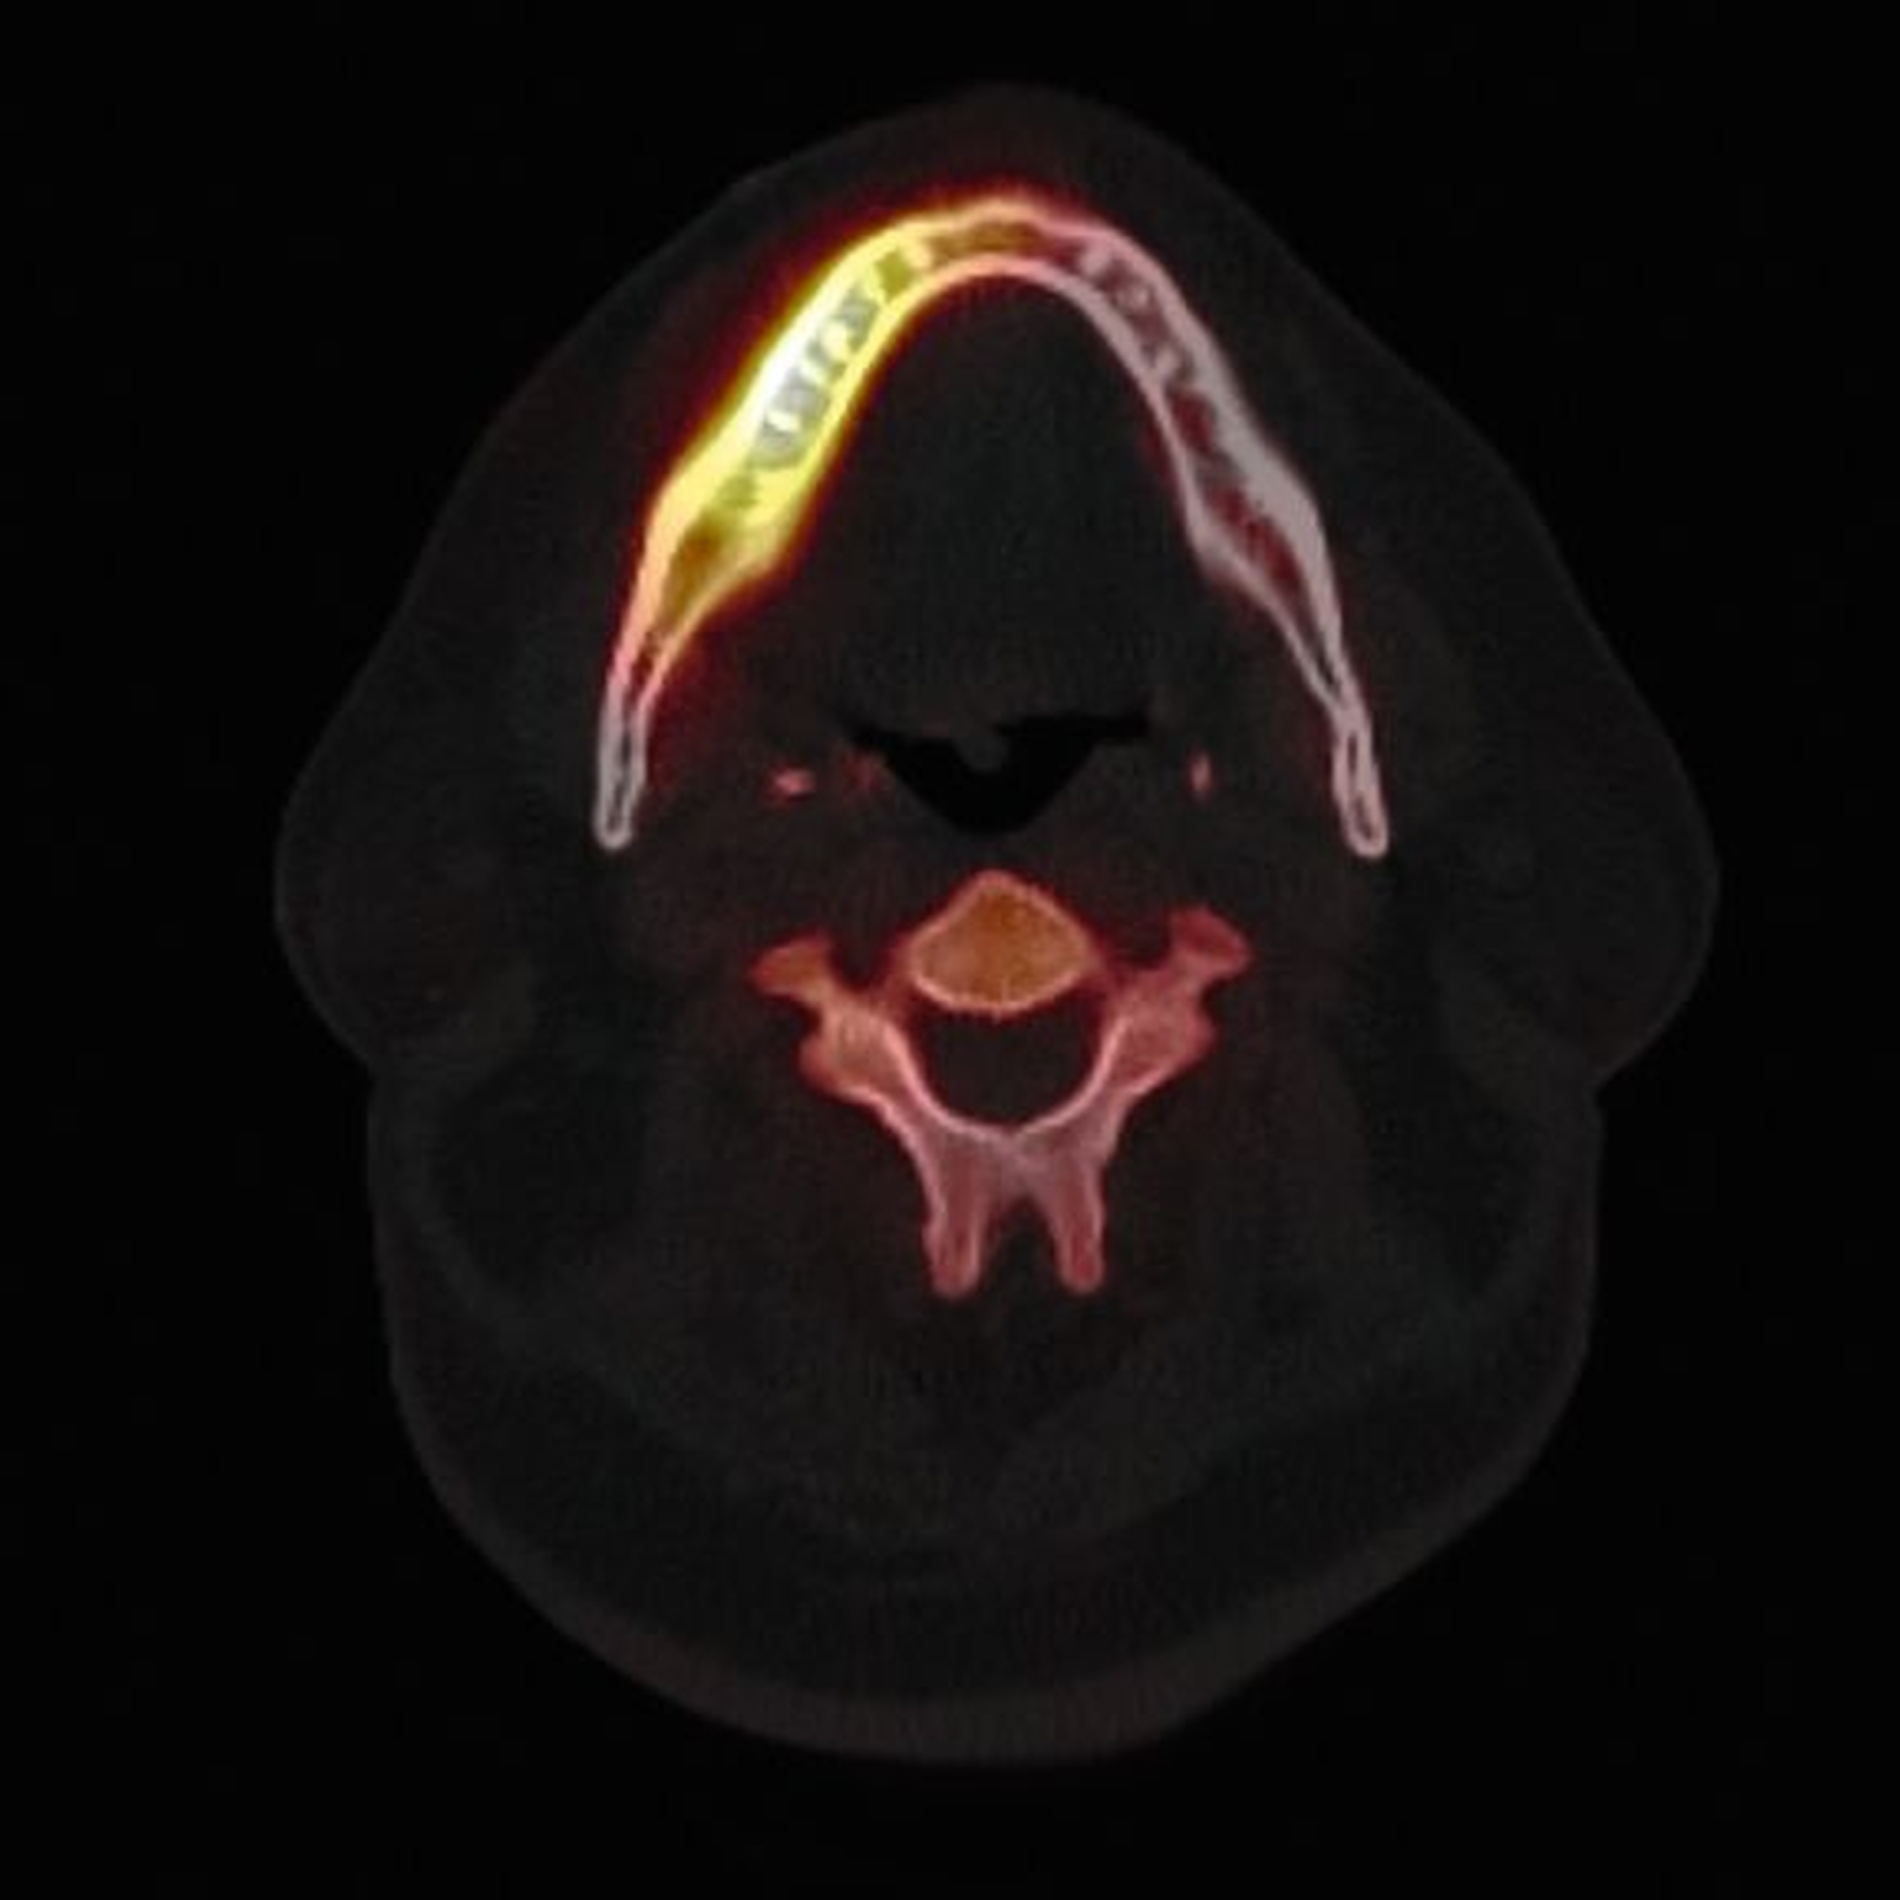

Zum Zeitpunkt der Erstvorstellung in der kieferchirurgischen Ambulanz zeigten sich keine klassischen Herpes-Zoster-Effloreszenzen im Gesicht. Eine antiresorptive Therapie oder Bestrahlung lag nicht vor, sodass eine Herpes-Zoster-assoziierte Osteonekrose im Sinne einer Ausschlussdiagnose festgestellt wurde. Anamnestisch bestand ein gut eingestellter Diabetes mellitus Typ 2 als potenziell immunkompromittierende Grunderkrankung. Die Knochenszintigrafie zeigte eine deutliche Stoffwechselsteigerung im betroffenen Bereich, vereinbar mit einer infizierten Osteonekrose.

Die Knochenszintigrafie zeigte in diesem Fall eine deutliche lokale Mehranreicherung, wie man sie in vergleichbarer Intensität auch bei Medikamenten-assoziierten oder Strahlenbedingten Osteonekrosen beobachten kann. Während bei diesen Entitäten aufgrund der chronischen Ischämie meist ausgedehnte, teils kontinuitätunterbrechende Resektionen erforderlich sind, unterscheidet sich die Pathophysiologie der Herpes-Zoster-assoziierten Osteonekrose grundlegend. Da hier eine vorübergehende, Virus-induzierte Vaskulitis vorliegt, sollte die szintigrafische Aktivität nicht überinterpretiert, sondern ein zurückhaltendes, reduziert-invasives chirurgisches Vorgehen gewählt werden. Der beschriebene Heilungsverlauf bestätigt die Effektivität des gewählten konservativen Vorgehens.